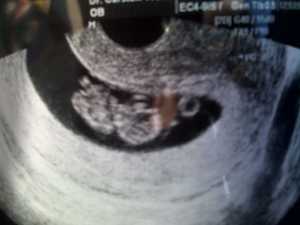

Vi får babyen opp på skjermen, og en forbauset lege utbryter «jøss! Det var da voldsomt mye bevegelse til å være bare 10 uker!» Han mente det var et veldig bra tegn, og det er ikke ofte han ser 10 uker gamle foster bevege seg så mye rund. MiniTiger sparket og slo og suttet på hånden sin. Søte gullet mitt! 🙂 Vi fikk beskjed om at alt ser bra ut, og at det var sikkert bare ekstremt sterke strekk-smerter i arrvevet mitt etter alle operasjonene. Så da er MiniTiger trygg, og da er mitt stakkars mamma-hjerte litt roligere! Jeg hater virkelig drama!!! Kan ikke være godt for helsen!

Jeg gir 5 stjerner for bildet, ikke for sykebesøket! Bra det går bra med mor og barn!! 😀

Ja er hun ikke søt?? 😀